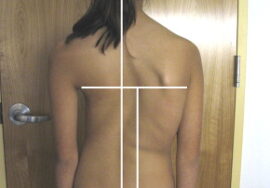

يعاني كثير من المراهقين من اعوجاج العمود الفقري المراهقي مجهول السبب (Adolescent Idiopathic Scoliosis – AIS)، وهو انحناء غير طبيعي للعمود الفقري غالبًا على شكل حرف C أو S. هذا الانحناء قد يؤثر على شكل الجسم ووضعية المراهق ويزيد القلق لدى الأهل حول صحة أبنائهم.

تقليل دوران الجذع (ATR): يقل التواء الجسم، ما يحسن مظهر الظهر عند النظر من الخلف.

إذا لاحظتِ علامات انحناء في ظهر طفلك، أو لاحظتِ عدم تماثل بين الجانبين، فلا تتردد الأن في استشارة مجانيه من طبيب متخصص.

إذا لاحظتِ علامات انحناء في ظهر طفلك، أو لاحظتِ عدم تماثل بين الجانبين، فلا تتردد الأن في استشارة مجانيه من طبيب متخصص.

إذا لاحظتِ علامات انحناء في ظهر طفلك، أو لاحظتِ عدم تماثل بين الجانبين، فلا تتردد الأن في استشارة مجانيه من طبيب متخصص.